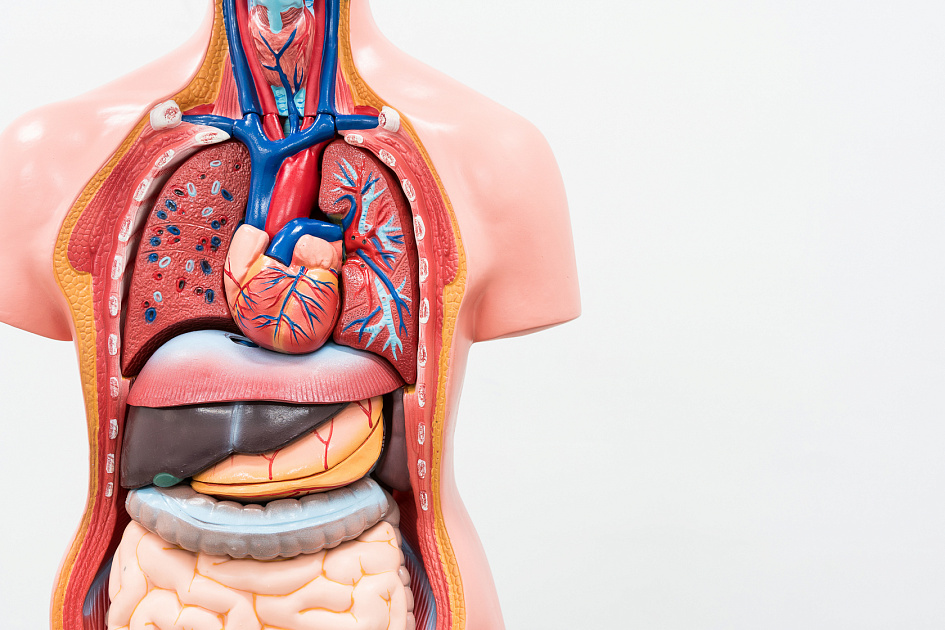

Другой важной частью в организме человека является его наружный покров- кожа. Кожа — наружный покров организма человека, защищающий тело от широкого спектра внешних воздействий, участвующий в дыхании, терморегуляции, обменных и многих других процессах. Кроме того, кожа представляет массивное рецептивное поле различных видов поверхностной чувствительности (боли, давления, температуры и т. д.). Является самым большим человеческим органом, так как кожа полностью покрывает тело человека. Ниже на рисунке представлены различные системы человека, а также из чего они состоят (рисунок представлен с помощью портала allmedicina.ru):

Рис. 2.5. Различные системы человека

На данном рисунке показаны различные важные системы человека с перечислением органов, которые участвуют в процессах этих системах. Читатель должен знать название системы, а также те органы, которые существуют конкретно в этих системах. Сами же системы выполняют разные функции, а именно:

Сами же органы каждой из систем будут рассматриваться подробно при изучении конкретных проблем с теми или иными внутренними органами (например, отравление, внутренние психические расстройства).